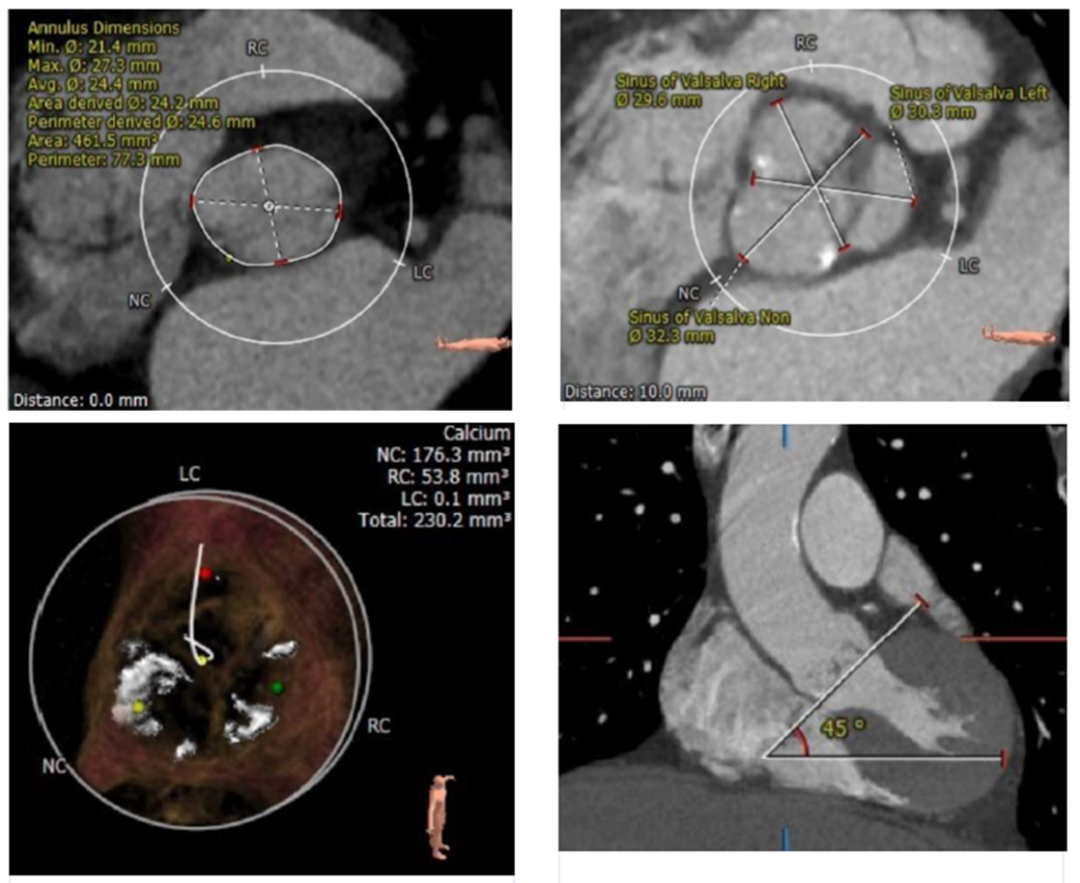

典型病例1

手术由首都医科大学附属北京安贞医院心内科周玉杰副院长、心外科张海波教授、心内科刘巍教授及其团队组成的TAVR心脏瓣膜团队共同完成。中国医学科学院阜外医院吴永健教授、四川大学华西医院冯沅教授、复旦大学附属中山医院潘文志教授等与会专家深度参与手术相关步骤的讨论和技术交流。

本次结构周转播手术难度较高,周玉杰副院长,张海波教授、刘巍教授通过超高的跨瓣技巧和精准定位释放,再次展现了首都医科大学附属北京安贞医院多学科交叉团队在处理危重复杂病人中的丰富经验,为广大线上观摩专家呈现了多台具有教育指导意义的TAVR病例,并且荣膺本届中国结构性心脏病周“最具贡献奖”。同时,周玉杰副院长也将TAVR患者PCI策略的安贞经验与与会专家分享。